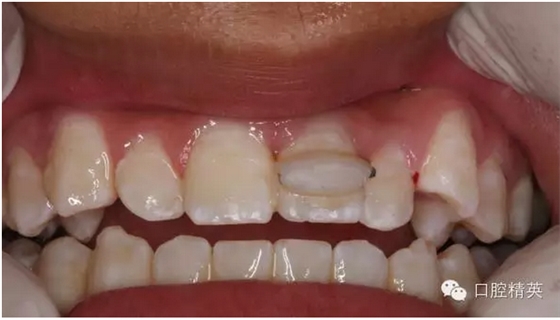

圖1.術(shù)前患者口內(nèi)像、牙槽窩輕度收縮、血凝塊穩(wěn)定、無(wú)滲出。

圖2.口內(nèi)整體影像